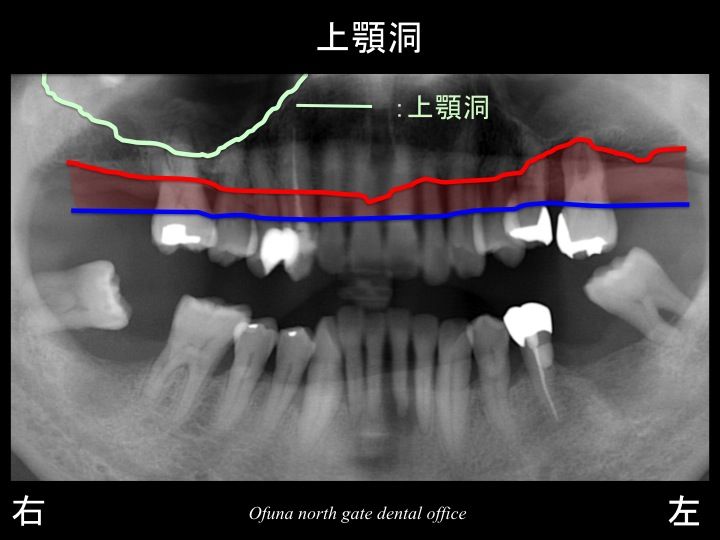

いつものように 骨吸収の状態を分かりやすくするために

骨吸収の状態を線で書いたのが以下のレントゲンになります。

青線が骨吸収を起こす前の骨の位置です。

赤線は、現在の骨の位置です。

さらに分かりやすくするために 骨吸収部位を赤色の領域で表します。

以下の緑線は上顎洞という空洞です。

緑線の内側は空洞なのです。

骨ではありません。

ただの 穴 です。

これも さらに分かりやすくするために、上顎洞 を緑色で表示します。

歯周病による骨吸収と上顎洞の存在により、残っている骨の高さが少なくなっていました。